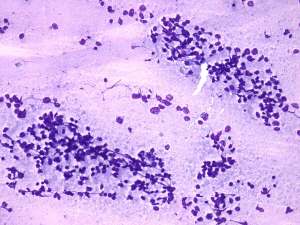

Cytology: suspicion of non Hodgkin lymphoma.

Biopsy was performed from the lesion and histopathology revealed large B cell lymphoma.

The cytological picture was identical with a small cell malignant tumor. Differential diagnostics included a metastatic small cell lung tumor and malignant lymphoma. The clinical presentation substantially decreased the likelihood of the former.